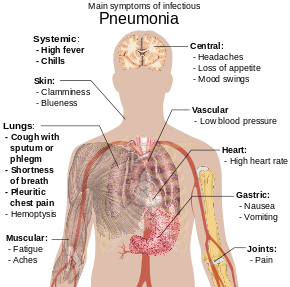

All about Typhoid fever

Typhoid fever is caused by Salmonella typhi bacteria. Typhoid fever is rare in industrialized countries. However, it remains a serious health threat in …